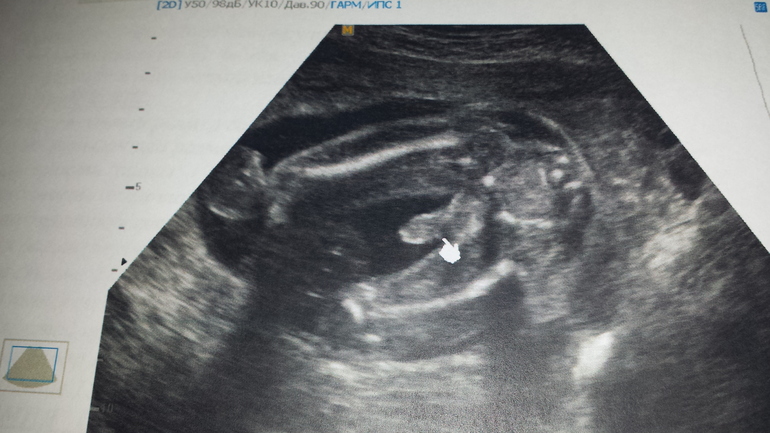

Решила написать отчетик. Нам сегодня уже 21 неделька. Были с папой на узи, малыш наш лежит попкой вниз и закрывается ручками. Записали его выкрутасы на диск, решили теперь по-немногу снимать наши приготовления к его появлению))) будет, что показать, когда подрастет))) по показателям-все в норме, по-прежнему опережаем срок почти на неделю)и нам подтвердили мальчика и папе показали, чтоб без сомнений, писюн на весь экран. Так хорошо в отпуске, были недельку на даче-там жара намного легче. Сейчас в городе-не знаем, куда скрыться. В понедельник мне снова на работку. Последний рывок и декрет... столько всего нужно успеть обустроить в квартире к появлению малыша... Активно закупаем с мамой приданое) муж сначала ворчал, сейчас тоже поддерживает и выбирает сам) Подсела на рисование по номерам, нарисовала сыночку картинку. Надеюсь понравится))) ну наверное пока все. Добавлю наши фотки) пузик-арбузик!